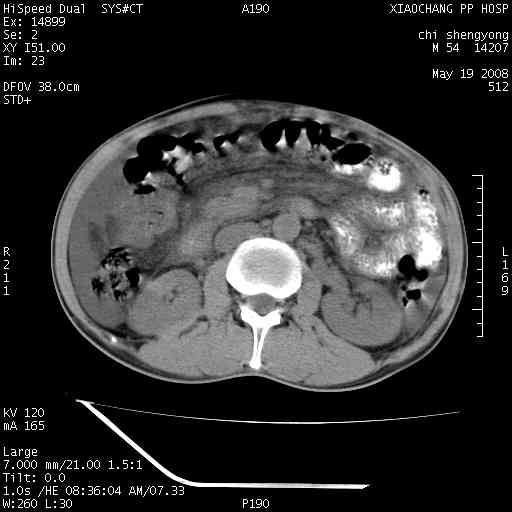

以下是引用zjzjr在2008-5-21 10:52:00的发言:[br]肝左叶巨块型肝癌伴门静脉左支瘤栓形成.肝硬化、腹水,胃底静脉曲张,脾术后改变。

以下是引用随光逐影在2008-5-21 16:20:00的发言:[br]1)肝左叶肝癌伴门静脉左支瘤栓形成,腹膜后淋巴结转移。2)肝硬化、腹水、胃底静脉曲张。3)胆囊炎。4)脾脏缺如,为切除术后所致。